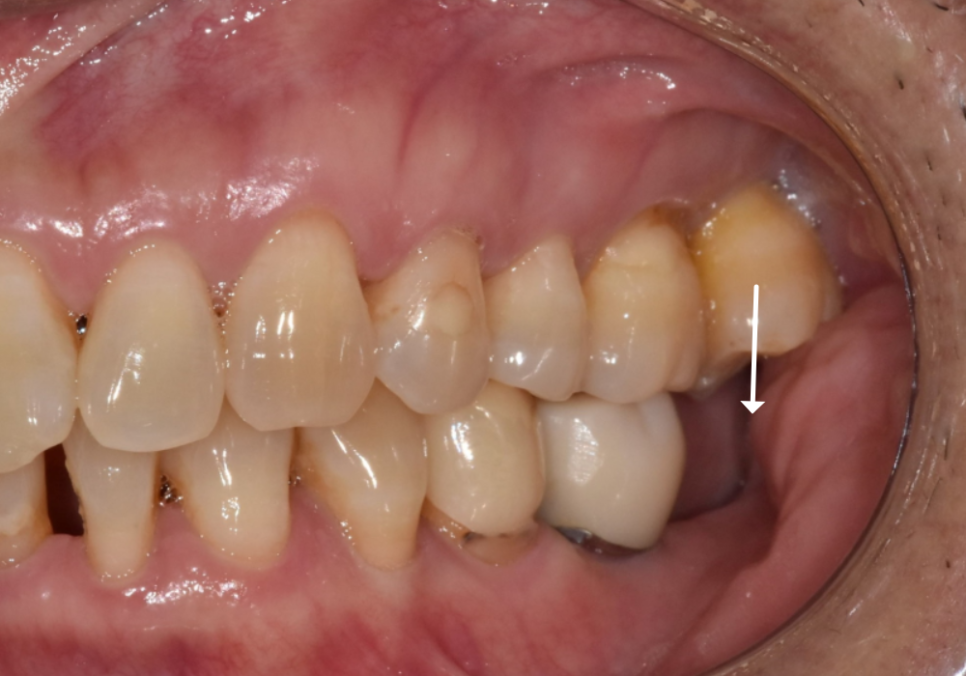

왼쪽 어금니는 맨 끝 치아가 상실된 상태라,

임플란트를 진행하기로 했습니다.

하지만 위쪽 치아가 아래로 내려온 탓에,

임플란트 머리(보철물)가

들어갈 높이가 너무 낮았는데요~

이대로 머리를 올리면 보철물이

자꾸 빠지는 부작용이 생길 수 있어요.

이럴 경우, 정출된 윗 치아를 다듬어서

#37 임플란트 머리가 들어갈 공간을

확보해야 합니다.